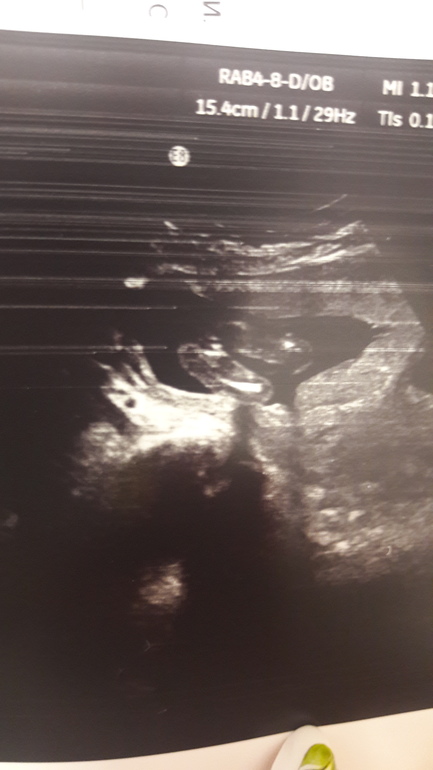

Пол малыша

УЗИ, КТГ, доплерДевочки,как вы думаете( или у кого похожее фото),девочка или мальчик? Сходили в 16-17 нед.Узист сказала,что 90% девочка,но к 20 неделям девочка может стать мальчиком.Муж не теряет надежды все-таки на сына.Мне то все равно и он,конечно,будет обожать дочку бесспорно,ребенок долгожданный.

Ну вообще на девочку похоже, но я не специалист, поэтому могу ошибаться. Просто что-то похожее сильно на половые губы видно

Девочка. У нас на таком сроке стручок торчал между ног) но бывает всякое...

Девочка. Писюн был бы виден уже на таком сроке. Хотя, никто не застрахован и всё может быть...